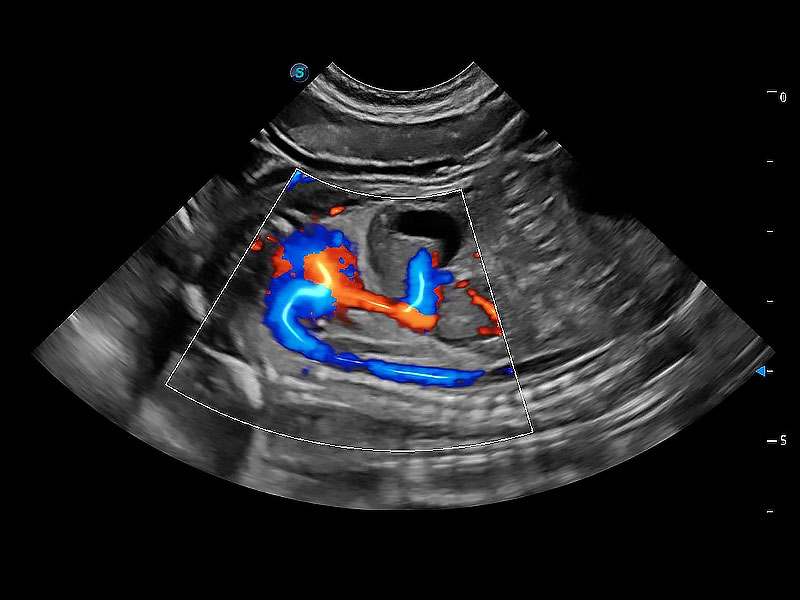

非线性融合造影成像充分利用谐波和基波信号,为难以观察的血流进行增强显像。可用于线阵、凸阵、微凸阵、相控阵探头。